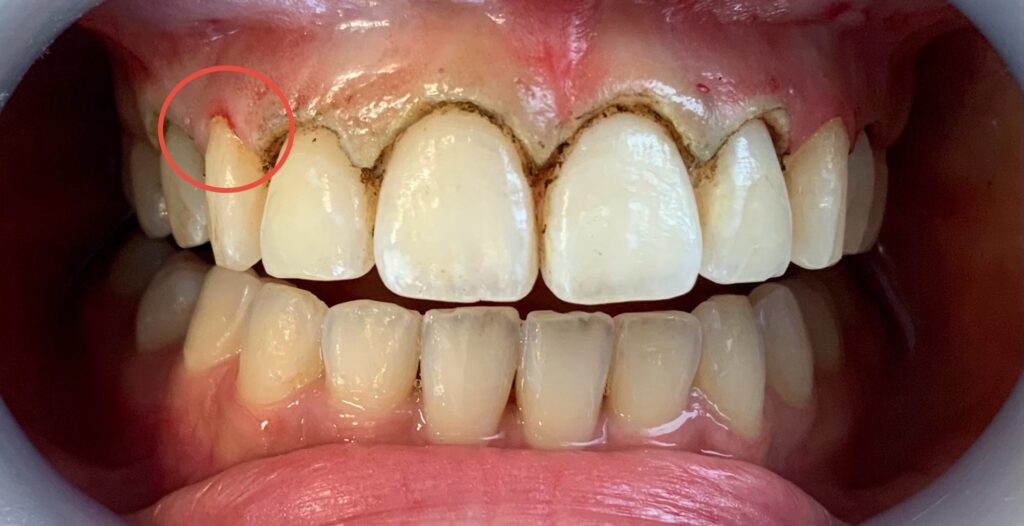

赤丸で囲っている部分。

切除していないのに、術後の写真は出血しています。

答えは、歯肉炎です。

犬歯は歯冠長延長はしていないのですが、術後に消毒薬をつけた綿球でなぞった際に、その刺激で出血しました。

ゴシゴシと力一杯こすった訳ではありません。

優しく拭いただけです。

歯肉炎で歯ぐきが腫れていると、柔らかい歯ブラシが当たった程度でも出血してきます。